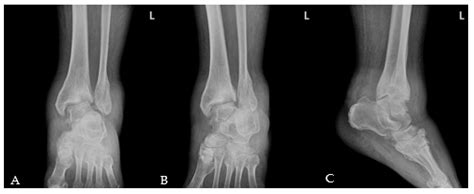

Diagnosis of Charcot Arthropathy Foot

Diagnosing Charcot arthropathy foot involves a combination of clinical examination and imaging studies. Healthcare providers will typically perform a thorough physical examination, assessing the foot for signs of swelling, redness, warmth, and deformities. They may also ask about the patient's medical history, including any history of diabetes or neuropathy.

Imaging studies are essential for confirming the diagnosis and assessing the extent of the condition. Common imaging studies include:

• X-rays: To visualize bone structure and detect any fractures or deformities

• MRI (Magnetic Resonance Imaging): To assess soft tissue damage and inflammation

• CT (Computed Tomography) scans: To provide detailed images of bone structure